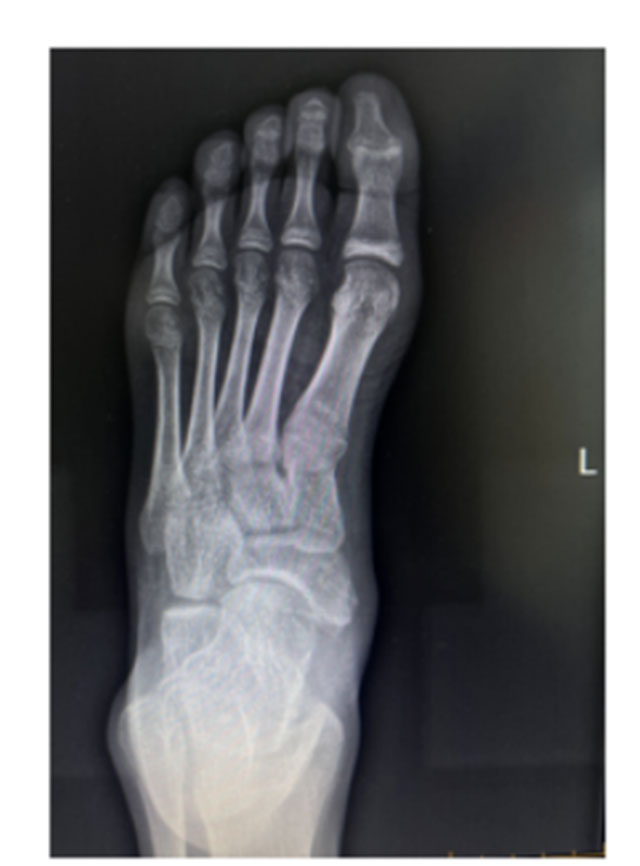

术后影像学复查

出院后经过4周休息及康复锻炼,小丽已重返运动场,继续备战体考,无不适反应。